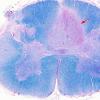

4C1 MS, spinal cord (Case 4) H&E 2X